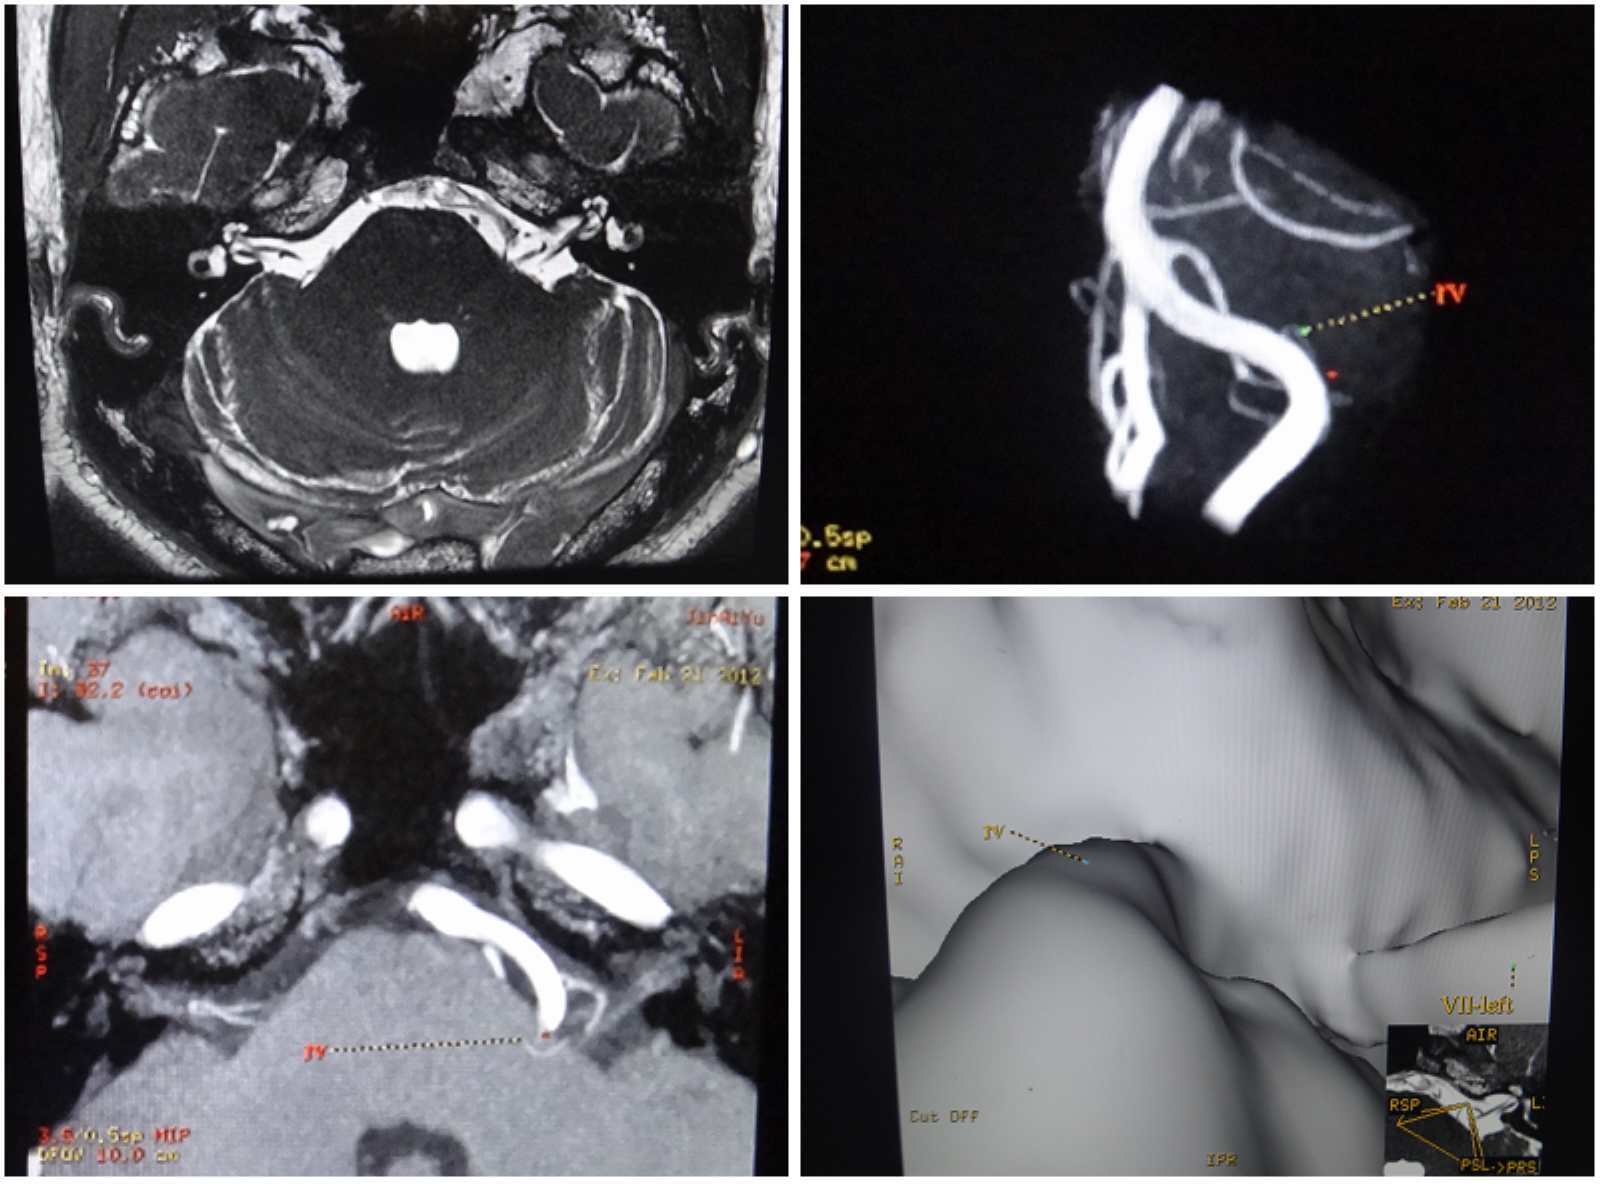

患者39岁,左侧面肌痉挛6年,服用药物卡马西平及盐酸硫必利无效,随着程度的加剧,接受了“微血管减压术”。“微血管减压术”出奇制胜,病人面部肌肉反复的不自主抽动消失。

面肌痉挛、三叉神经痛的发病时间顺序是有规律可循的。绝大部分患者首先发生面肌痉挛,然后发生三叉神经痛,考虑可能与椎基底动脉的迂曲硬化有关。椎基底动脉连接部位常于桥延沟,与面神经较靠近,易于先压迫面神经而造成面肌痉挛。随着动脉硬化的发展,以及随年龄增长而发生的不同程度的脑萎缩,扭曲硬化的椎基底动脉还会压迫三叉神经而造成三叉神经痛。

术前检查